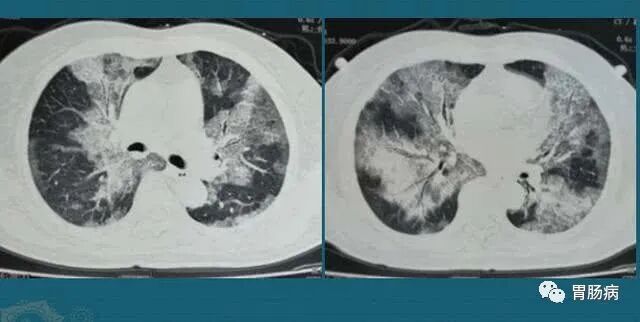

正常情况下肺部是由肺泡组成的,肺泡里边充满了空气,进行CT或者是X线检查时,它的影像表现应该是黑色区域。但如果肺泡里出现炎症和感染有渗出液和炎性细胞的时候,肺泡就被这些渗出液或者炎性细胞所填充,射线就穿不透,在影像学的表现上就出现了白色区域,就是大家说的“白肺。”

国家卫生健康委提示:首先可以明确的是,现在出现的所谓“白肺”与原始毒株和疫苗接种没有关系,并且当前的流行优势毒株仍然是奥密克戎毒株,这方面的信息,中国疾控中心专家在之前的新闻发布会上已经进行了回应。我们近期也注意到,在网络上关于白肺的信息。给大家先介绍一下什么叫白肺,白肺是肺部影像学表现的一个口语化描述。我们知道,肺部是由肺泡组成的,肺泡里面充满空气,进行CT或者X线检查的时候,射线穿过肺泡,影像表现是黑色区域,但是当肺泡里出现炎症或感染,有渗出液和炎性细胞的时候,肺泡就被这些渗出液和炎性细胞所填充,射线就穿不透,在影像学上出现白色区域。这个白色区域反映出来的是渗出物的影像学表现,并不是说肺脏组织实体变成了白色。随着渗出液的吸收、炎症的消退,白肺的表现也会逐渐消退,肺部的影像学表现会逐步恢复为黑色区域。并不是说只要肺部出现了炎症就都叫白肺,白肺应该是比较严重的肺炎表现。一般来讲,肺部的炎症比较重,渗出的比较多的时候,也就是白色影像区域面积达到了70%到80%,在临床上大家口语化称为白肺。所以不是只要出现了炎症就是白肺。这个阶段患者会出现低氧血症或呼吸窘迫。这类患者在临床上,尤其是高龄合并严重基础疾病的患者可能出现,但是这样的患者占比非常低。我们也注意到,现在网络上大家说的白肺有的不是真正的白肺,有的也没有达到很严重的程度,把它误称为白肺。